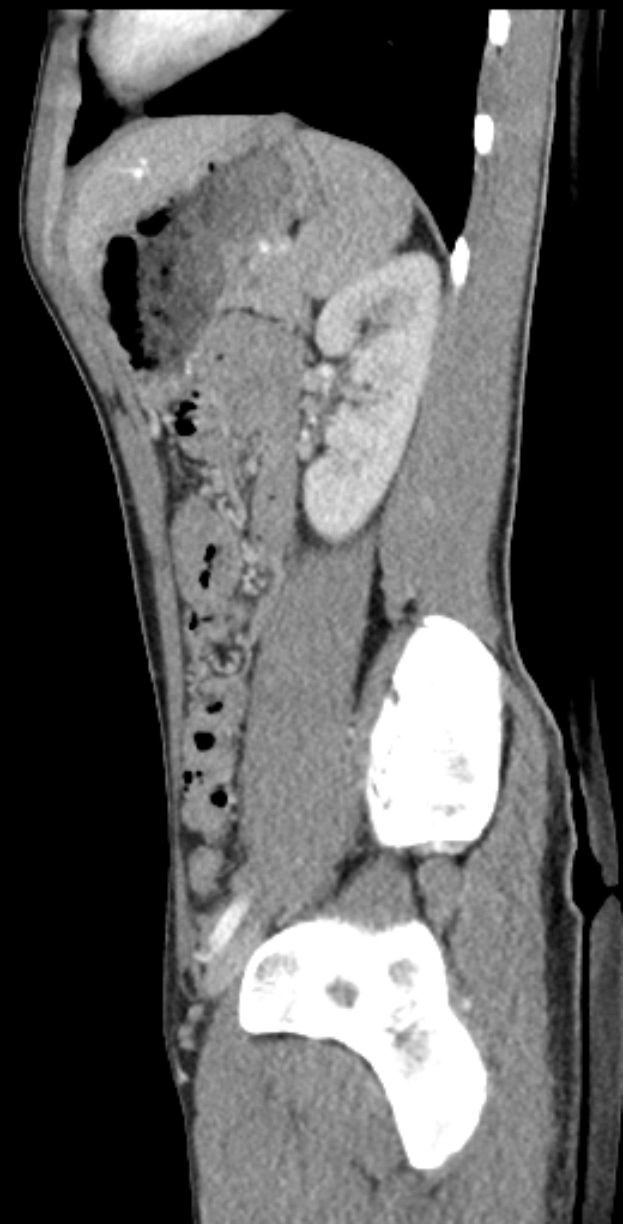

Eine MRT-Aufnahme eines Knies, die einen Bruch in der Mitte zeigt, umgeben von einem dunklen Hintergrund.Hiltrud Bolnbach